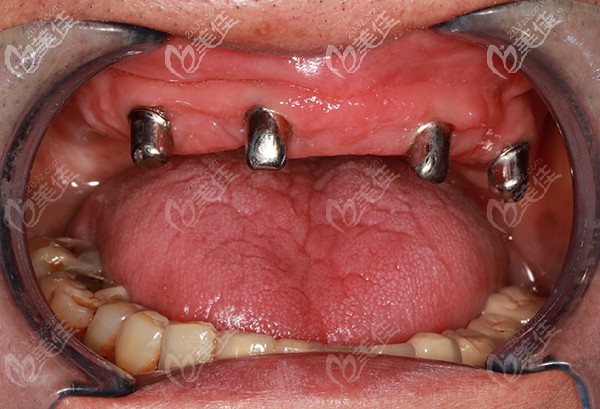

種植牙植入后

種植后口內(nèi)檢查照片

半口種植不需要為每一顆牙齒都植入種植體,我爸做的是allon4,也就是只需要4顆種植體的種植牙技術(shù),便可以進行半口牙(12-14顆牙齒)的種植。